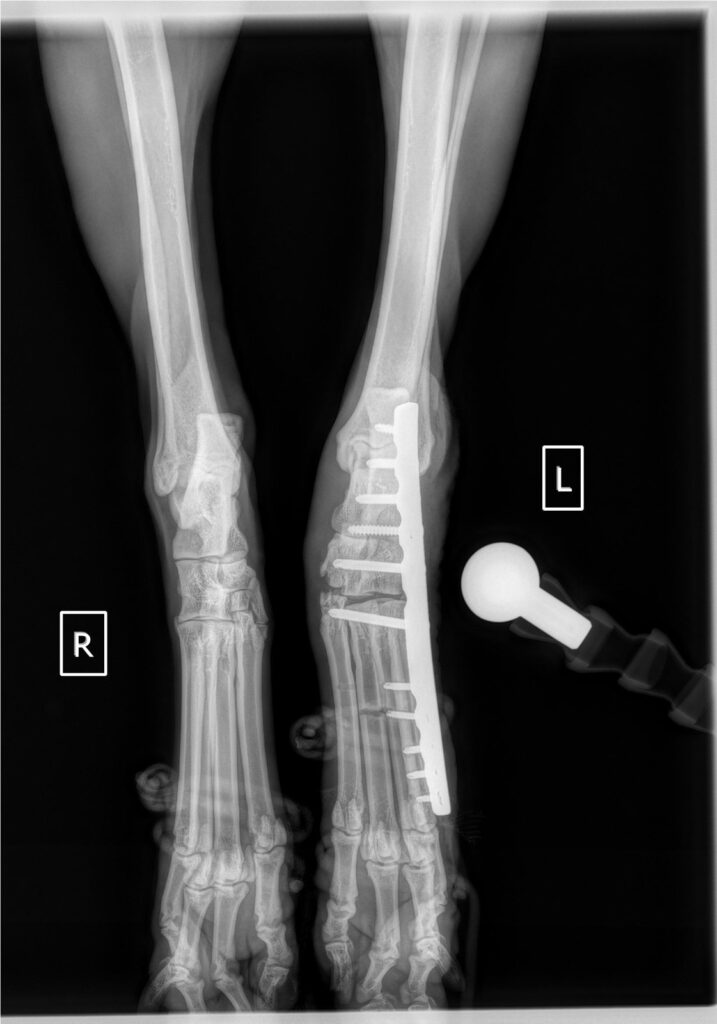

מרכז כרמל-ים הוא בית חולים וטרינרי לחירום ומומחים הממוקם בכפר הנוער שפיה ופועל 24/7 לאורך כל השנה. המרכז מתמחה ברפואה דחופה, אשפוז תחת השגחה רפואית מלאה ומגוון שירותי מומחים כגון כירורגיה, הדמיה וקרדיולוגיה, ללא עיסוק ברפואה מונעת שגרתית.